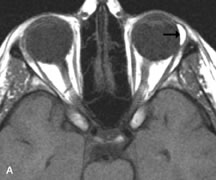

Metastatic Tumors

Breast carcinoma metastatic to the orbit has been demonstrated to be hypointense to the surrounding orbital fat on T1-weighted studies and hyperintense on T2-weighted images and has an affinity to the extraocular muscles (Fig. 20).50,64 The MRI characteristics of prostate carcinoma metastatic to the orbit have been described as involving the greater and lesser wing of the sphenoid, orbital roof, and optic canal. Diffuse bone hypertrophy with isointense or slightly hyperintense tissue on T1-weighted images represents the osteoblastic carcinomatous bone infiltration. Contrast enhancement is variable on T1-weighted and fat-suppressed images.65

Fig. 20. A. T1-weighted MR scan demonstrates nodular enlargement of both medial rectus muscles (arrows). B. T1-weighted fat-suppressed contrast-enhanced scan confirms the presence of small metnstatic deposits within the muscles (open arrows).

Most other metastatic tumors also have a lower intensity signal on T1-weighted images and appear to displace or infiltrate normal orbital structures; however, their signal characteristics are variable on T2-weighted MR images.66 Many metastatic tumors demonstrate bright contrast enhancement with Gd-DTPA.